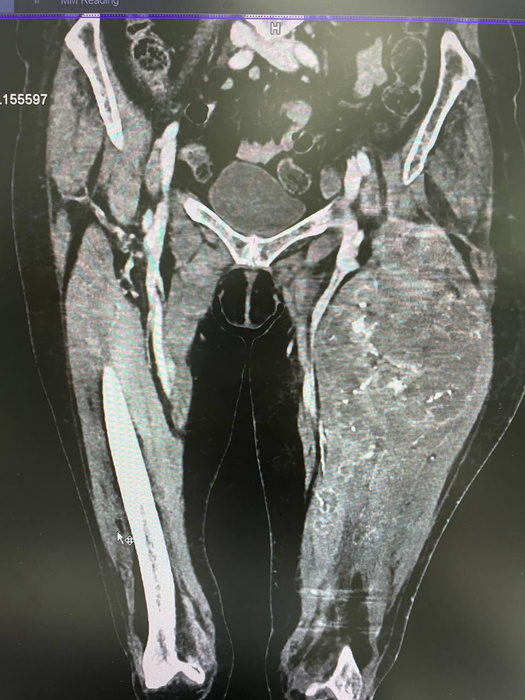

Головка правого бедра